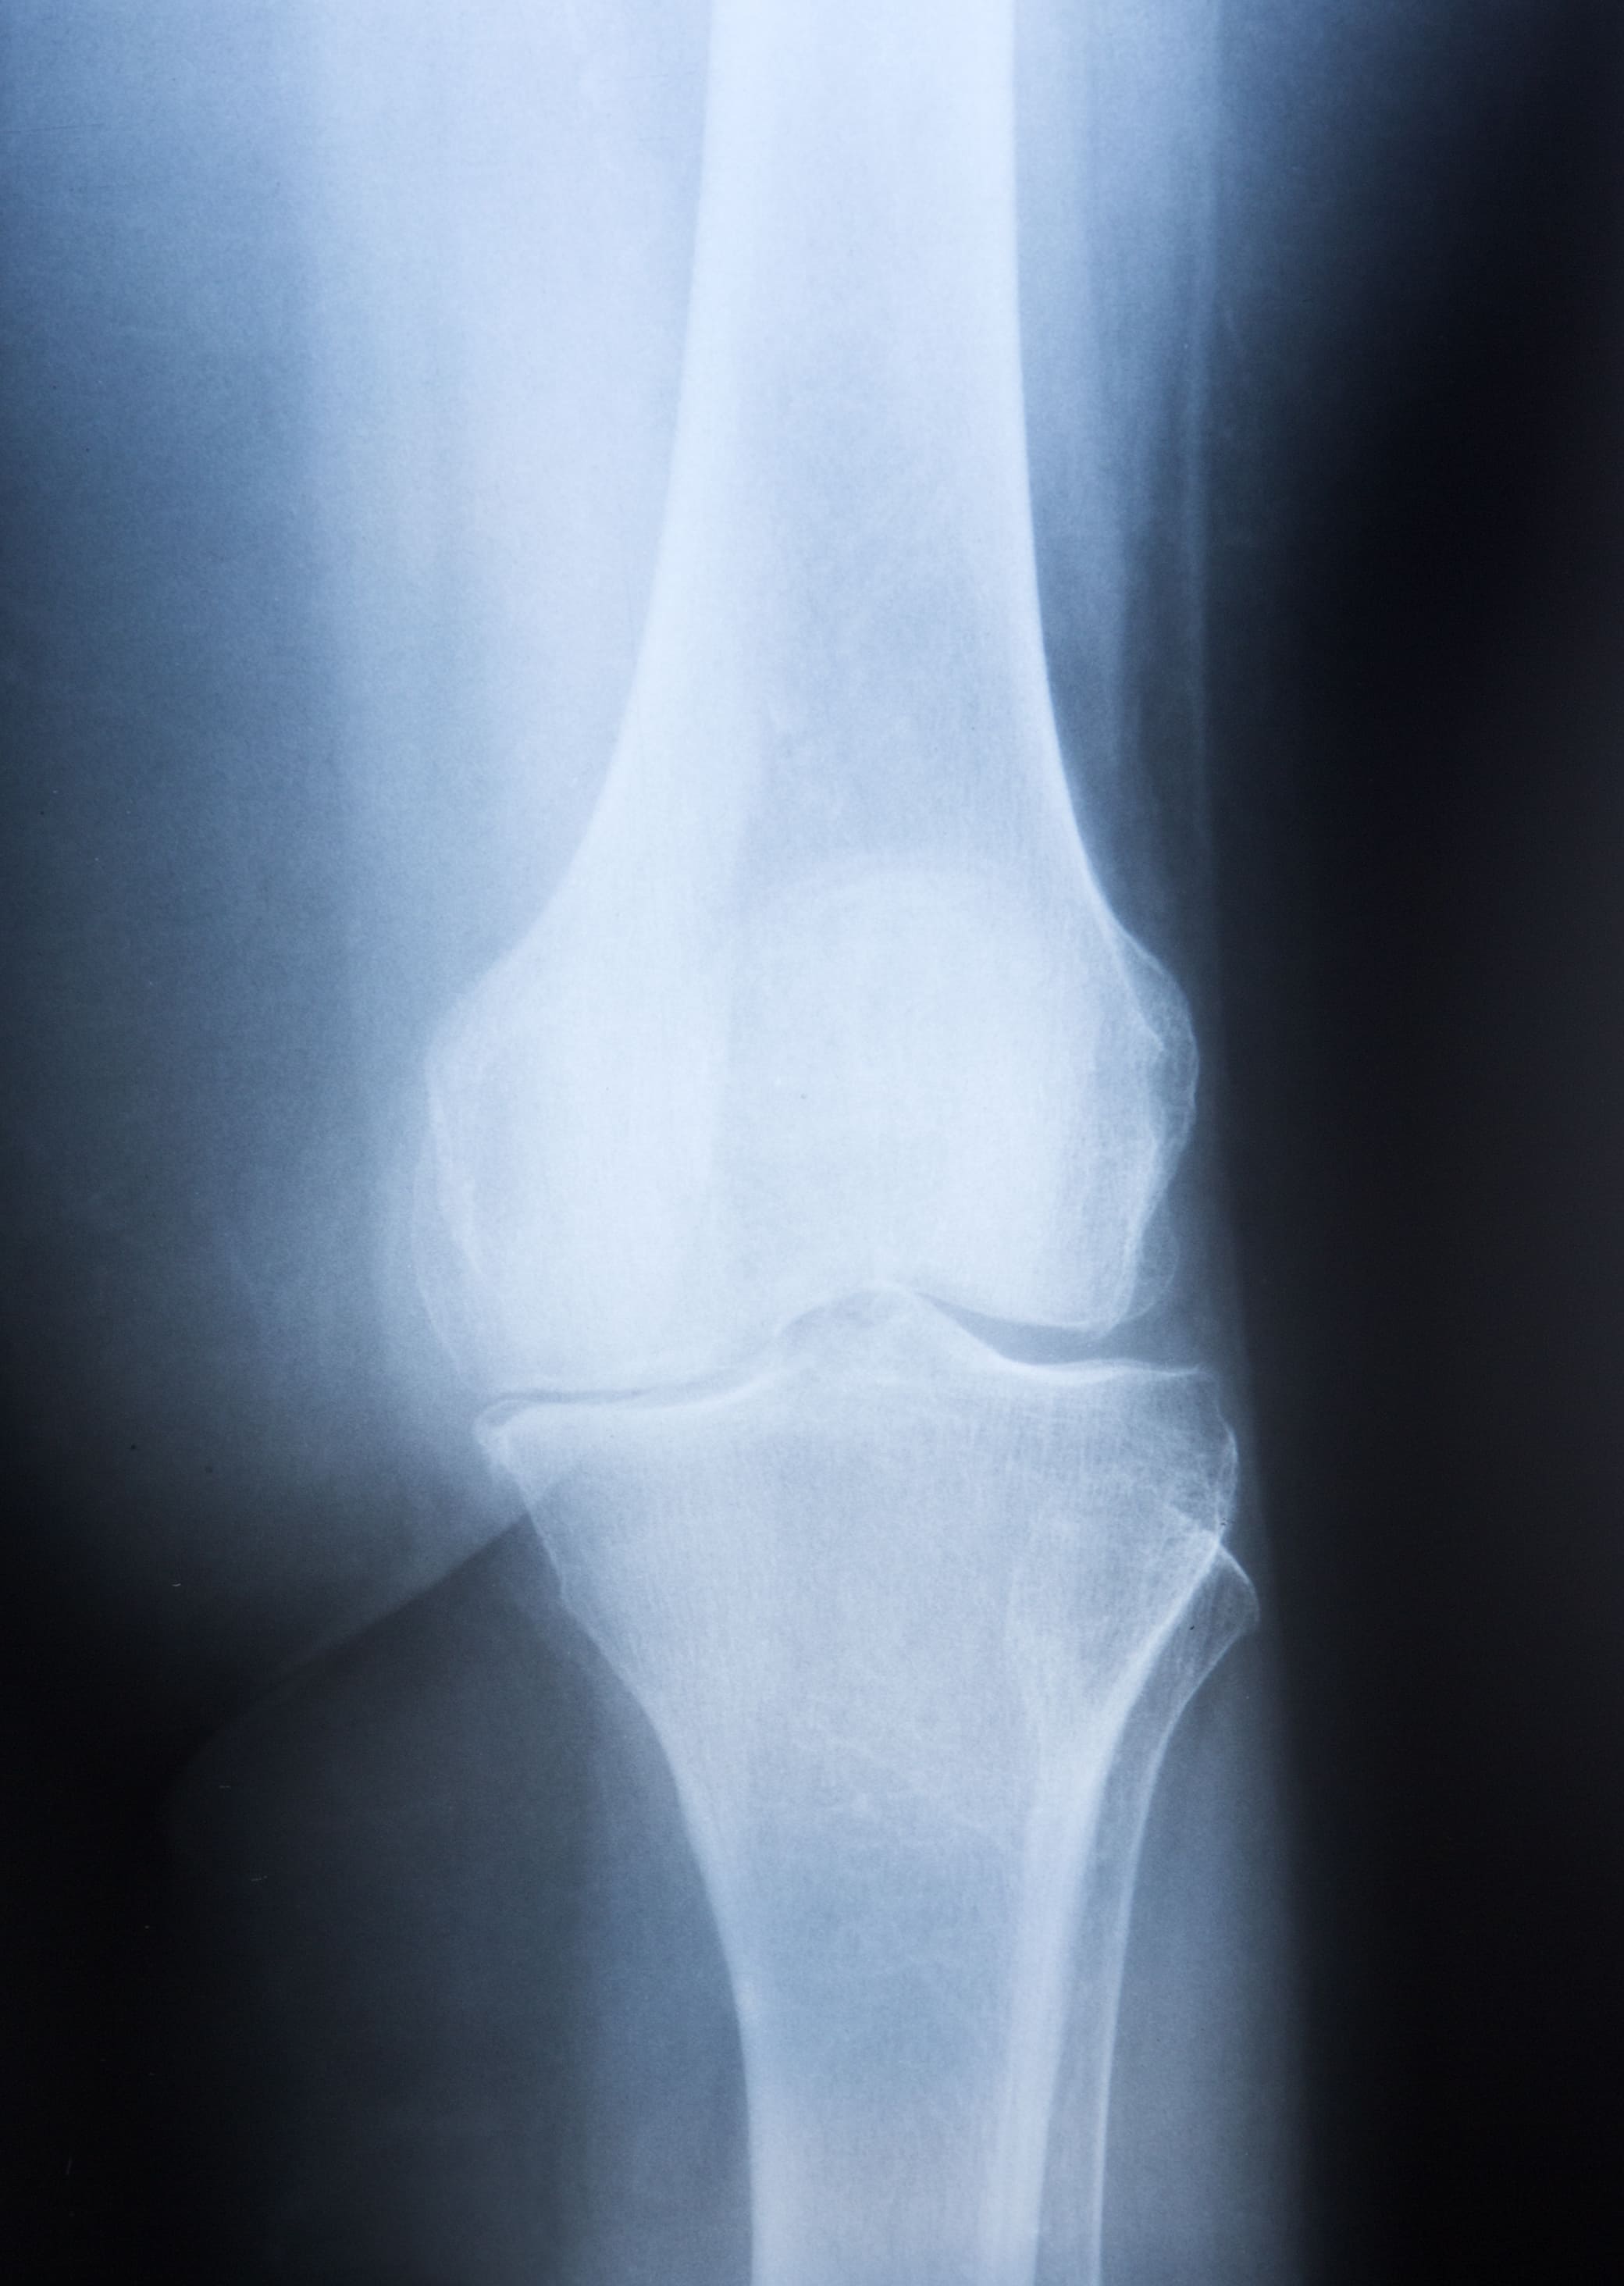

L'arthrose dégénérative n'est pas qu'une maladie articulaire liée à l'âge. C'est une atteinte progressive du cartilage qui s'installe dans les genoux, les hanches, la colonne ou la main, et qui transforme chaque mouvement en défi.

L'arthrose est une maladie articulaire dégénérative qui touche progressivement le cartilage, ce tissu souple et protecteur qui permet aux articulations de bouger sans douleur. Lorsque ce cartilage s'use, les os se rapprochent, frottent entre eux et provoquent des douleurs, des craquements, une raideur et parfois un véritable handicap. Loin d'être un simple effet du vieillissement, l'arthrose est une pathologie à part entière, dont l'évolution varie fortement d'une personne à l'autre.

L'arthrose touche principalement les articulations sollicitées au quotidien. Les genoux, les hanches et les mains représentent les zones les plus concernées, suivies de la colonne lombaire et cervicale.

Avec le temps, des déformations visibles apparaissent, particulièrement au niveau des doigts avec les nodosités caractéristiques, ou du genou qui peut se déformer petit à petit. L'ostéophytose, aussi appelée "becs de perroquet", en est une manifestation fréquente.